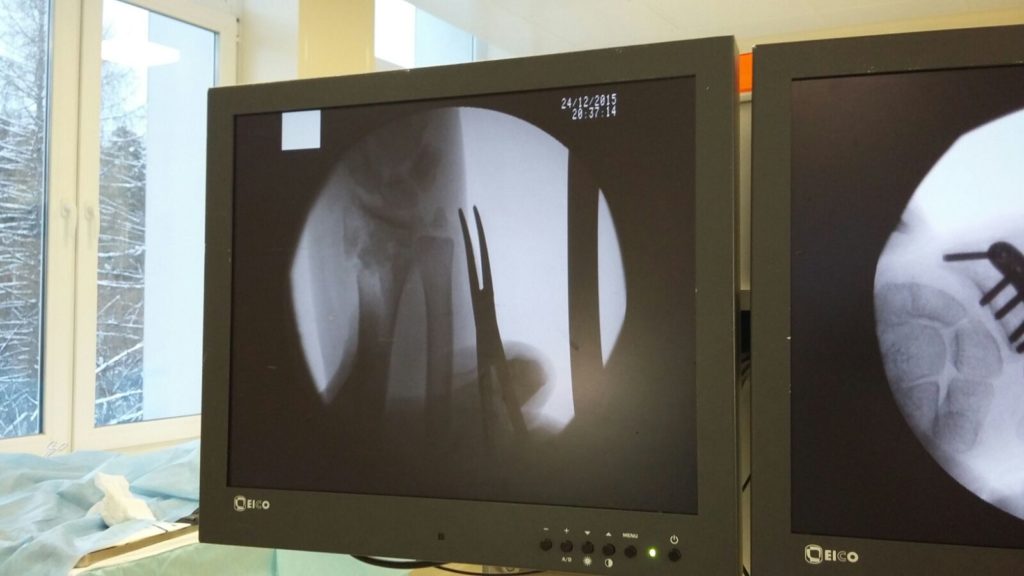

Операция - открытая репозиция, остеосинтез лучевой кости пластиной с костной ксенопластикой материалом "Остеоматрикс". На контрольных снимках в три месяца имеется консолидация перелома, миграции фиксатора нет, имеется остеоинтеграция ксенопластического материала.